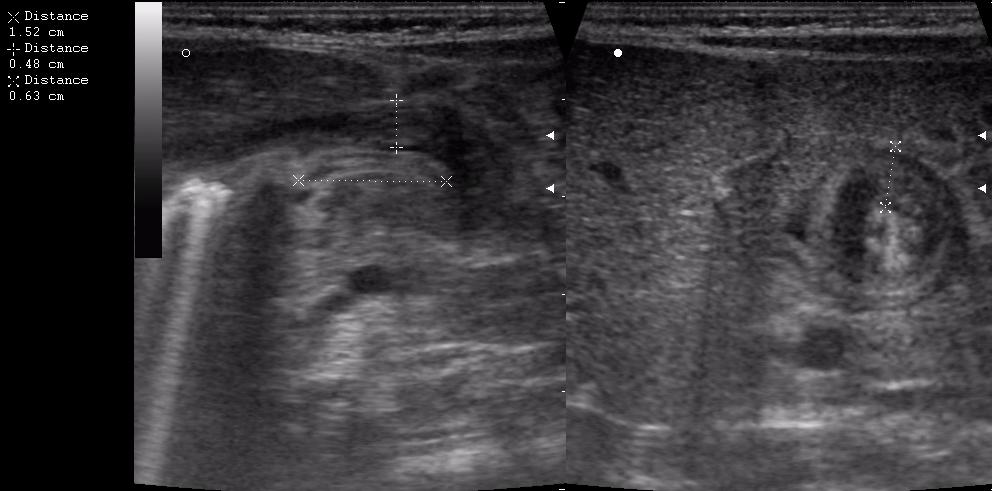

Ребёнок 1 месяц 10 дней от родy, с отсуствием прибавки в весе.

Hypertrophic pyloric stenosis.

Criteria:

1.Pyloric channel > 12 mm in length

2.Muscular layer thickness > 3-4 mm

3.Donuts sign at transverse scanning